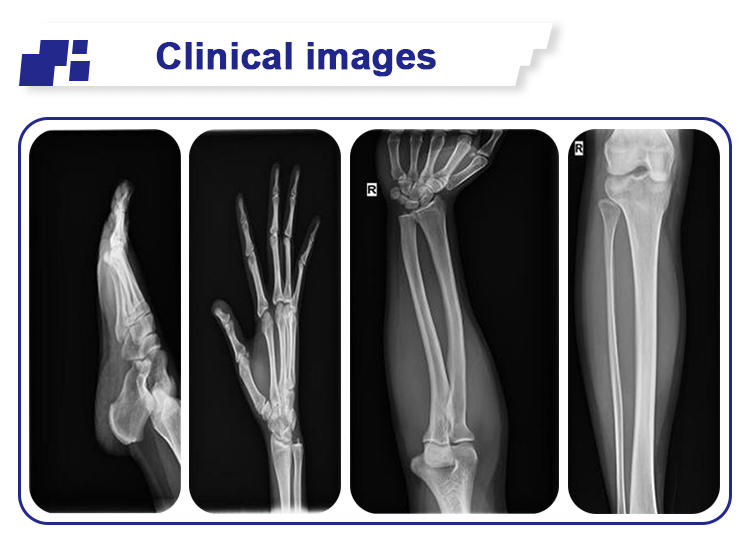

Mobile Portable Digital X Ray Equipment Radiography Diagnosis 100mA LCD Screen Images |